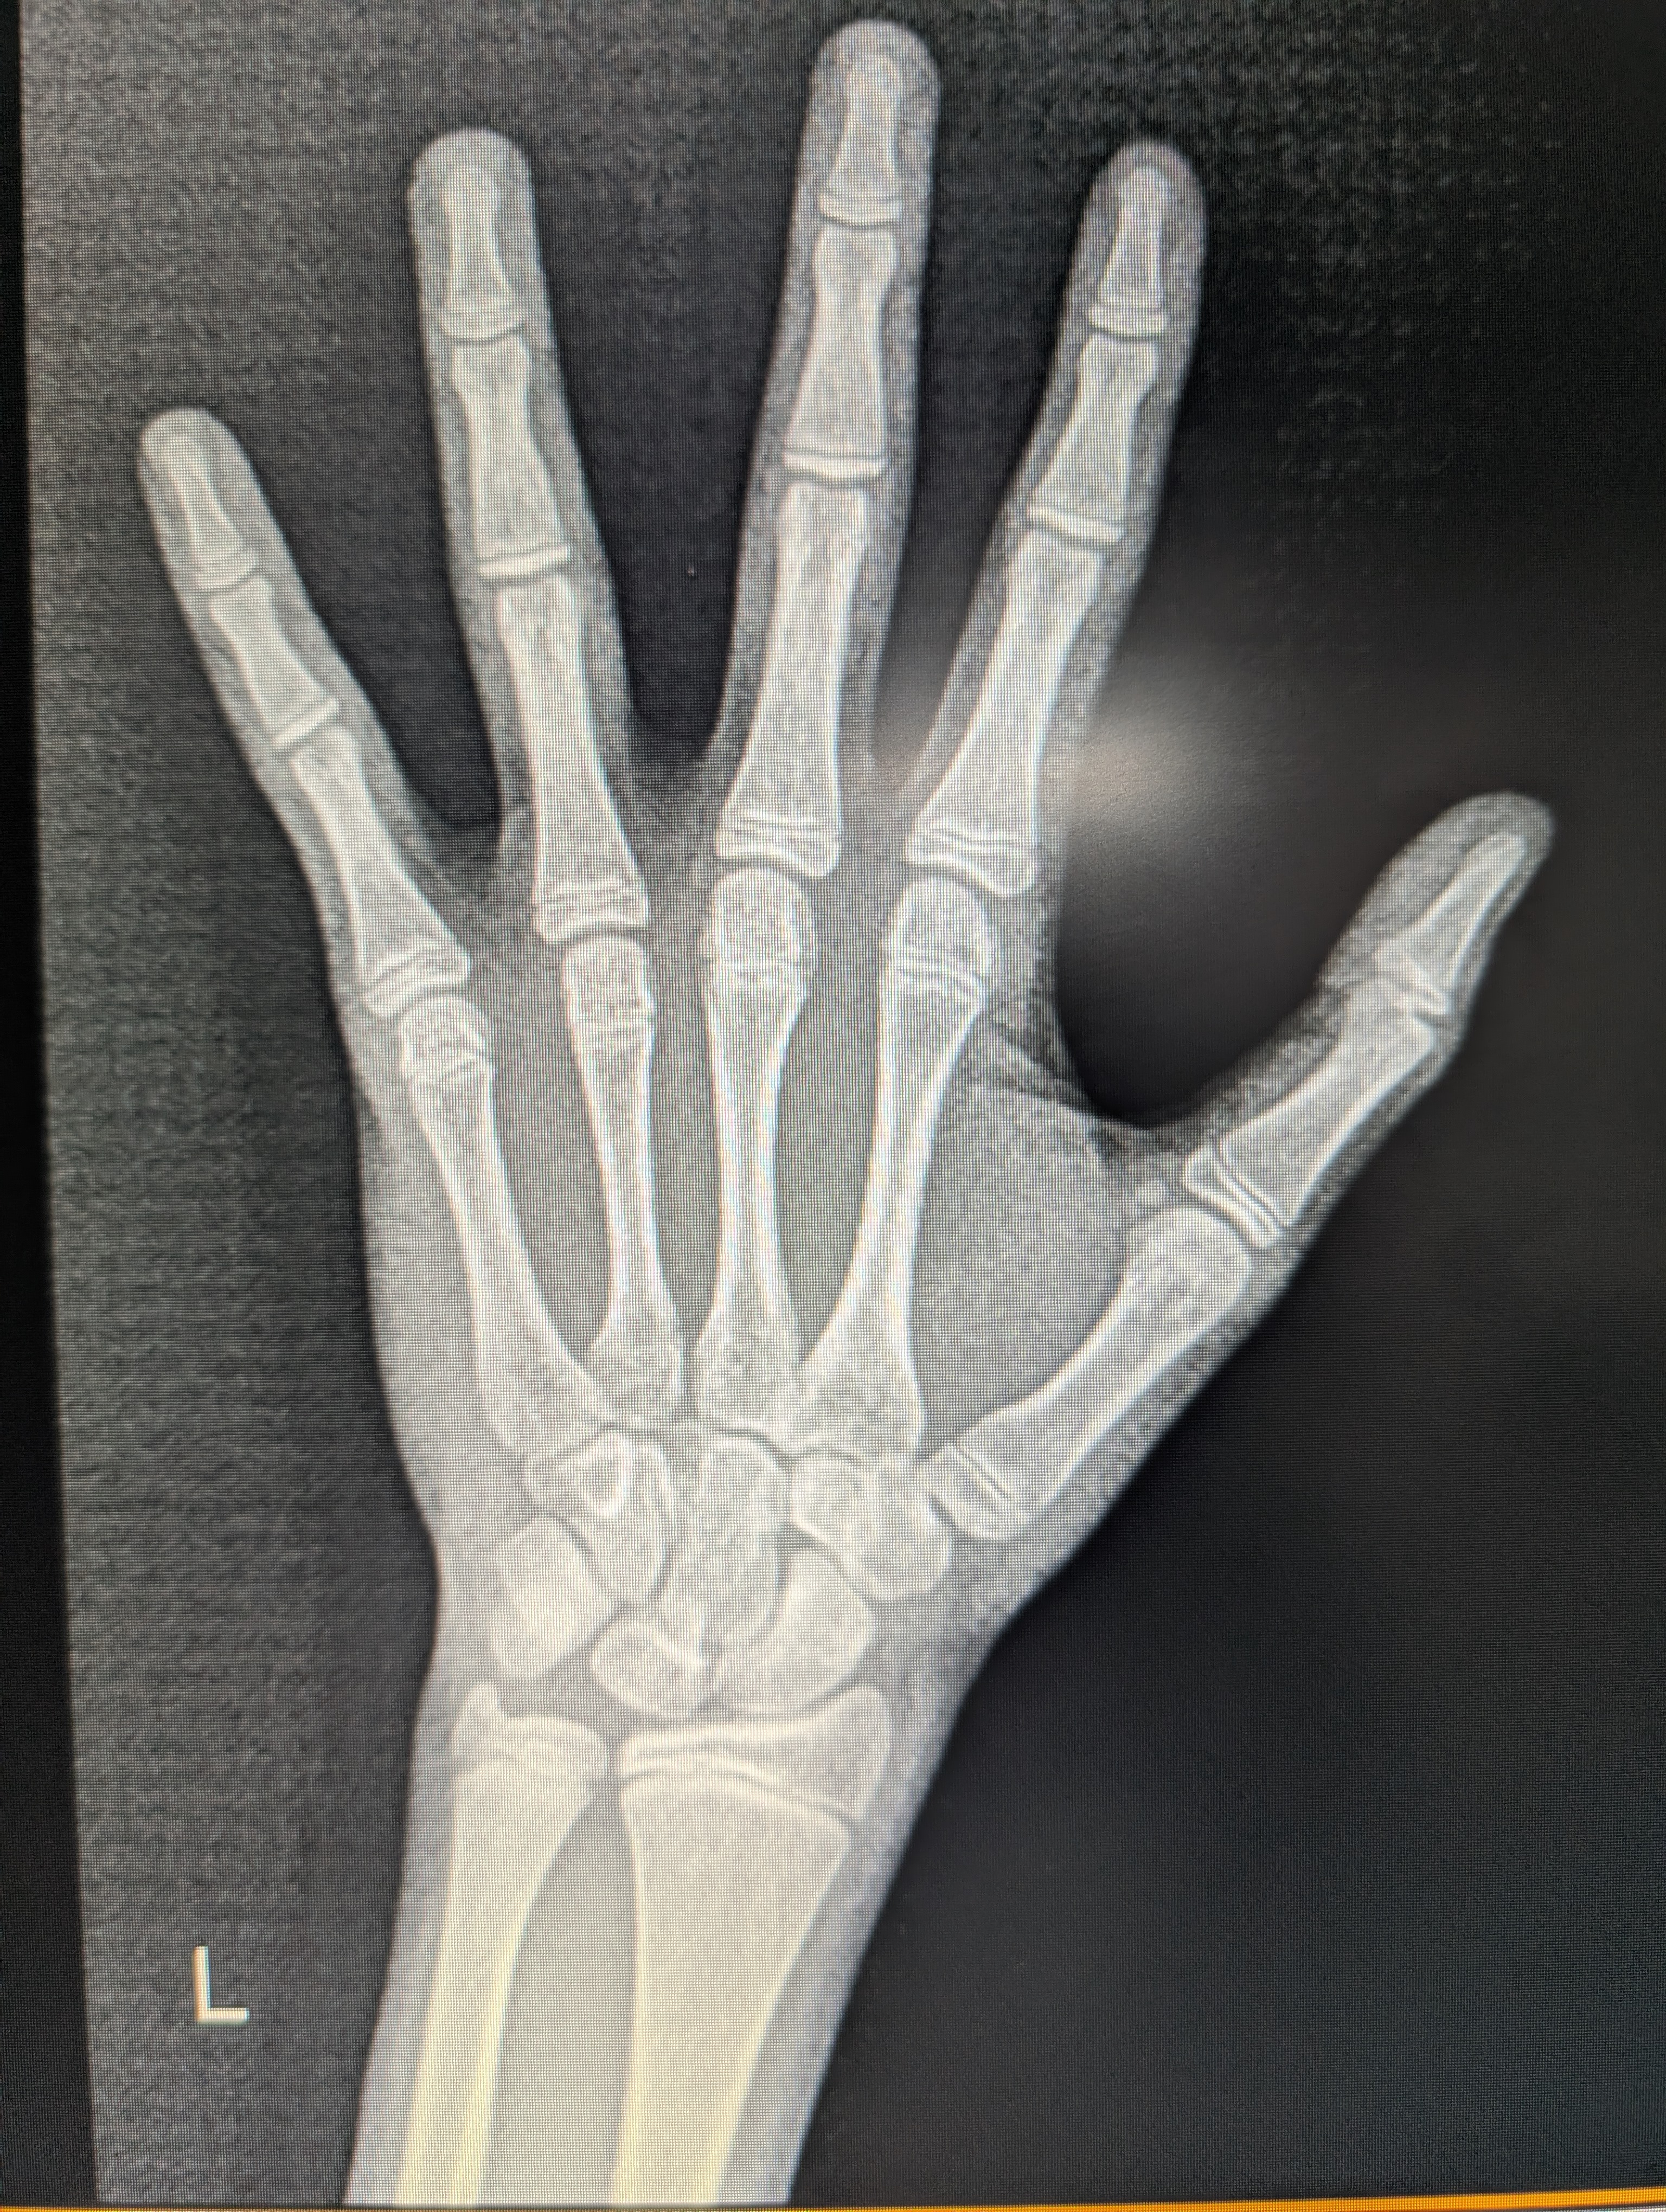

Holy shit 1 year is a lothould I take an AI, my Boneage is delayed like ~1.25 years.

yessir, Google reverse image and you won't find it anywhere. Should I take an AI, my Boneage is delayed like ~1.25 years. Getting HGH and test soon

Yeah, but it catches up, my bones grow faster, a year ago my bone age was an additional .5 delayed, I matured like 15 months in 12 months and will only get faster from hereHoly shit 1 year is a lot

Hop on ai if you wanna slow the bone maturation while keeping the same height speedYeah, but it catches up, my bones grow faster, a year ago my bone age was an additional .5 delayed, I matured like 15 months in 12 months and will only get faster from here